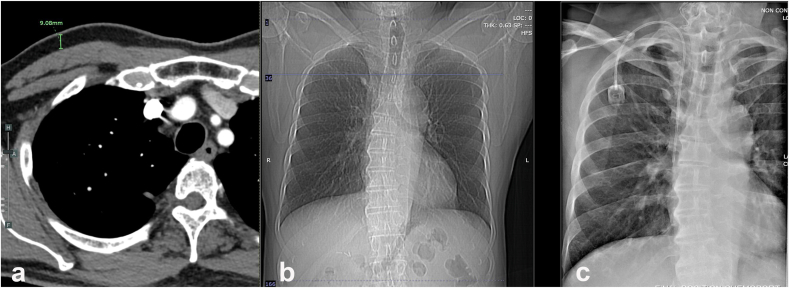

This study retrospectively reviewed 363 patients with chemoport insertion between May 2018 and May 2022. The patients were classified into three groups, with 121 patients in each group, based on the tertiles of subcutaneous fat thickness measured in the computed tomography (CT) scan. The incidence of short-term and long-term complications, including dislocation, infection, and malfunction, were obtained and compared between the three groups. The risk factors of chemoport-related complications were analysed in multivariate analysis.

The incidence of infection in the low, middle, and high subcutaneous fat thickness groups were 1.7%, 3.3%, and 0%, respectively (P = 0.131). No short-term complications occurred in this study group. After one year of follow-up, 11 patients (3.0%) had long-term complications; 6 patients (1.7%) developed chemoport infection, while five patients (1.4%) had chemoport dislocation. In multivariate analysis, the risk of dislocation was significantly higher when insertion was performed via the left internal jugular vein (OR = 9.87, P=0.033).

The thickness of subcutaneous fat does not significantly correlate with the incidence of chemoport infection, and placement of the port on the left side of the chest wall via the left internal jugular vein is the risk factor for chemoport dislocation.